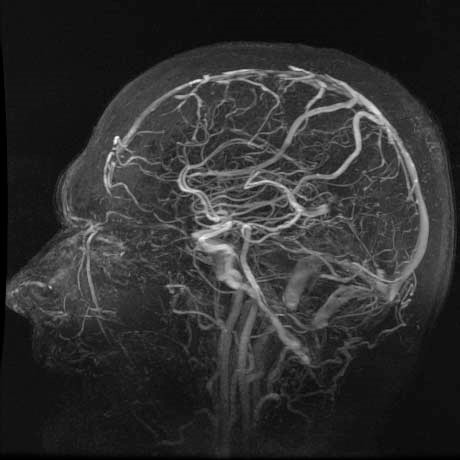

MRV stands for magnetic resonance venography. It is an MRI studies of the blood vessels. MRVs are used to assess abnormalities in the blood vessels of patients with a history of stroke, aneurysm, heart disease, and atherosclerotic vascular disease.

If you experience frequent headaches, an MRV of the head may be recommended to detect or rule out blood clots in the brain. An MRV of the chest is used to detect blood clots or blockages in the main arteries leading to the heart, and an MRV of the abdomen checks for blood clots or blockages in the liver.